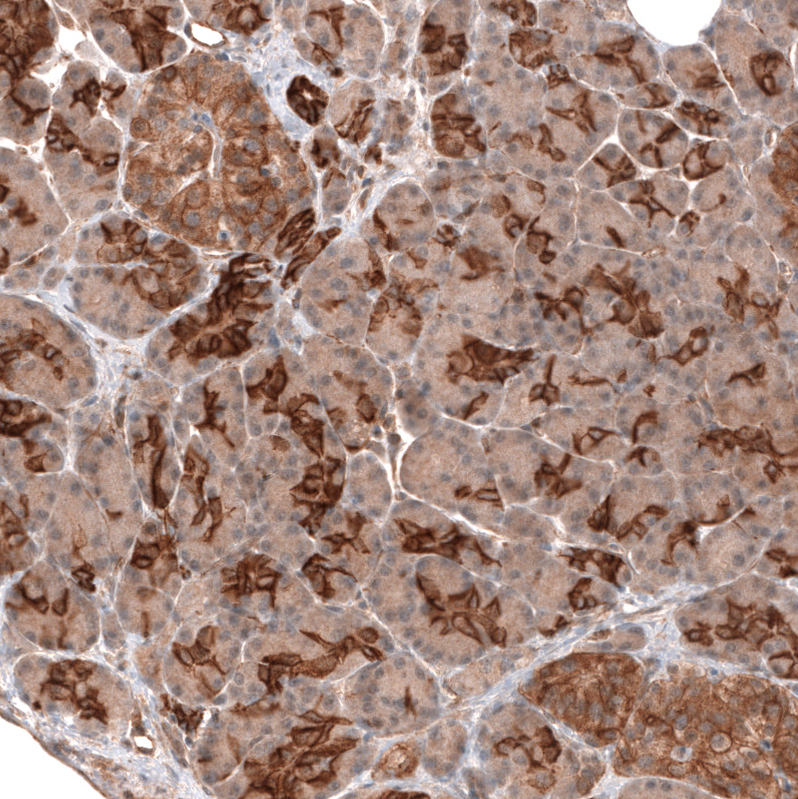

Immunohistochemical staining of human ovarian cancer (high grade serous carcinoma) shows strong membranous positivity in tumor cells.